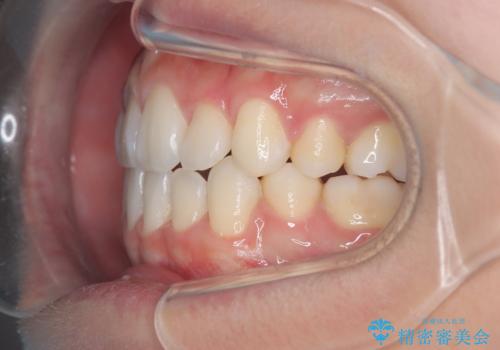

- 治療計画

上下左右の第一小臼歯を抜歯し、クリアブラケット(白い装置)とメタルワイヤーを使用して矯正を開始。初期には犬歯のアーチ内への整列を優先し、中盤からは前歯と奥歯の咬合関係の調整を進めました。審美性に優れた装置を使用したことで、治療中も目立ちにくく、見た目へのストレスが少ない点も評価されています。全体の治療は1年半で完了し、見た目・噛み合わせともに大きく改善。患者本人も「短期間でここまで変わるとは思わなかった」と満足されていました。